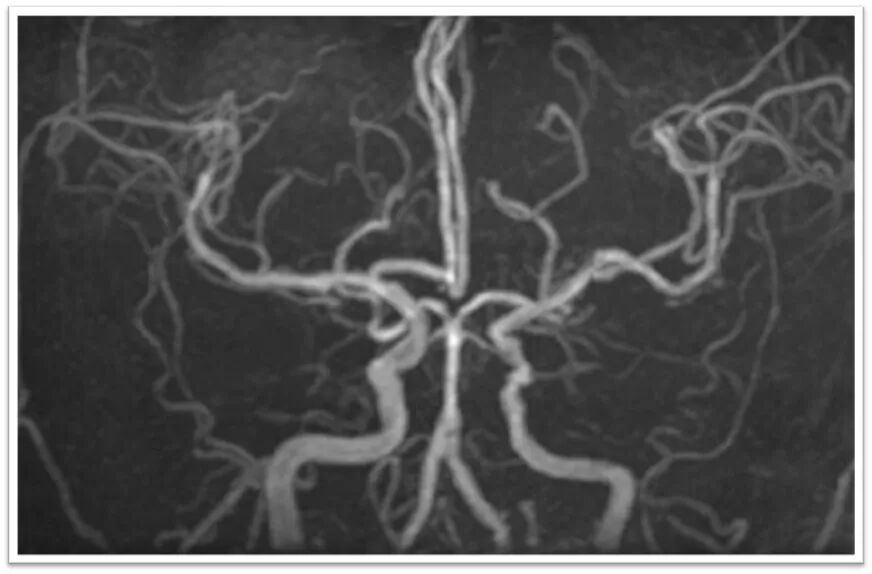

图3:头颈部MRA提示左侧颈总动脉闭塞,右侧双干大脑前动脉,左侧后交通动脉未开放;